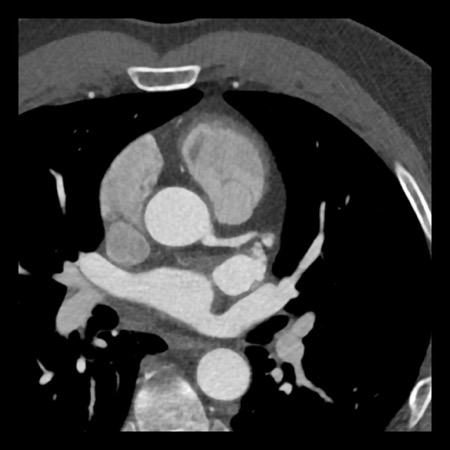

case 1 – CAD-RADS 2/P1

First, scroll through the scan.

Not all images are included. Some images without any abnormalities are skipped

from the series.

How would you describe the findings on the coronary CTA?

The findings are:

- Agatston score of

this patient was 14 (P1). Please, also note the calcification of the aortic valve. - Some partially

calcified and calcified plaques are present in the LAD with mild stenosis

(25-49%). - Calcified-plaque in

the LCX causing minimal stenosis (<25%). - Non-calcified

plaque in the distal RCA causing minimal stenosis (<25%). - This patient classifies

as CAD-RADS 2/P1, which means no further workup is needed.